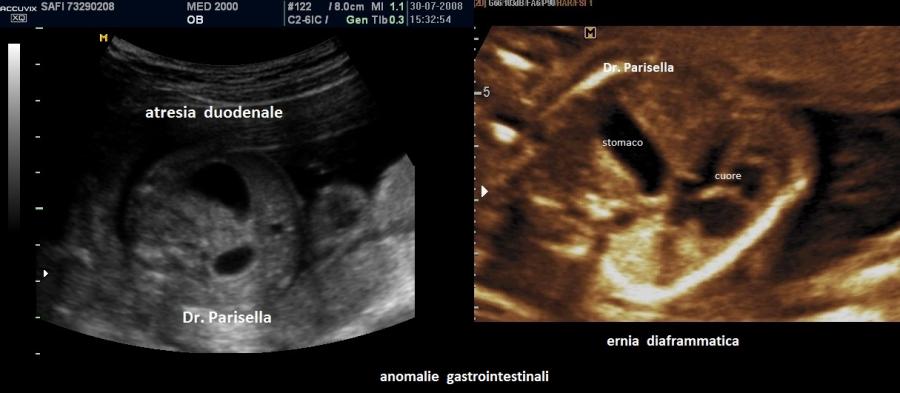

La Sindrome di Smith-Lemli-Opitz appare tipicamente caratterizzata da anomalie cranio-facciali, anomalie del SNC, anomalie scheletriche, anomalie genitali, cardiopatie congenite, anomalie gastrointestinali.

Frequenti anche le anomalie gastrointestinali come stenosi pilorica, reflusso gastroesofageo, malrotazione del colon.